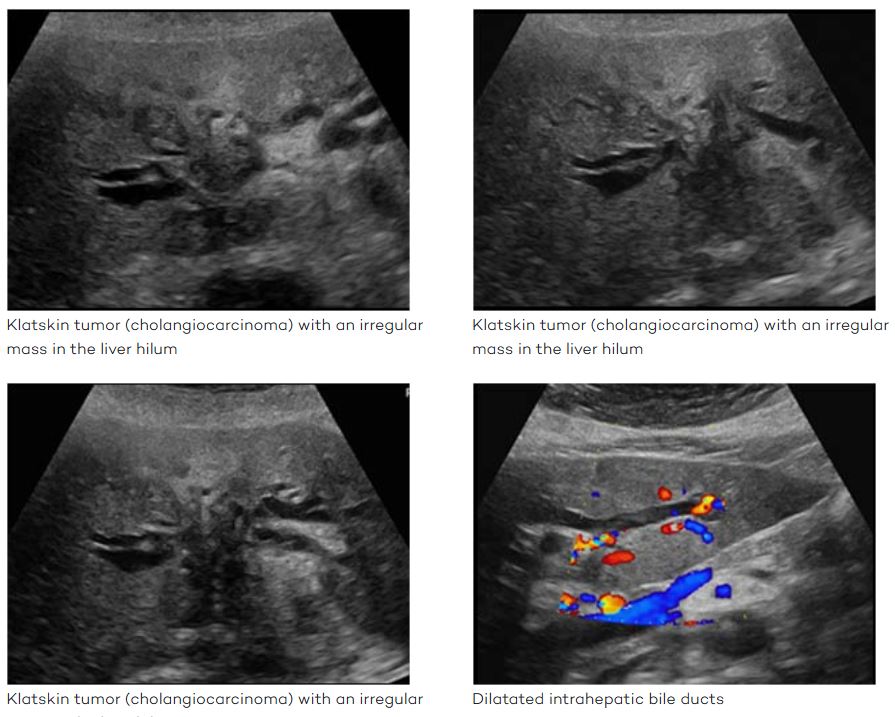

another name for hilar cholangiocarcinoma

Klatskin tumor

specific type of cholangiocarcinoma

jaundice, pruritus, and elevated cholestatic liver parameters.

Begins in the right or left bile duct and then extends into the proximal duct and distally into the common hepatic duct and contralateral bile ducts.

Tumor may extend outside of the ducts to involve the adjacent portal vein and arteries.

Chronic obstruction leads to atrophy of the involved lobe.

Majority of patients die within 1 year of diagnosis

isolated intrahepatic duct dilation.

Hilar Cholangiocarcinoma